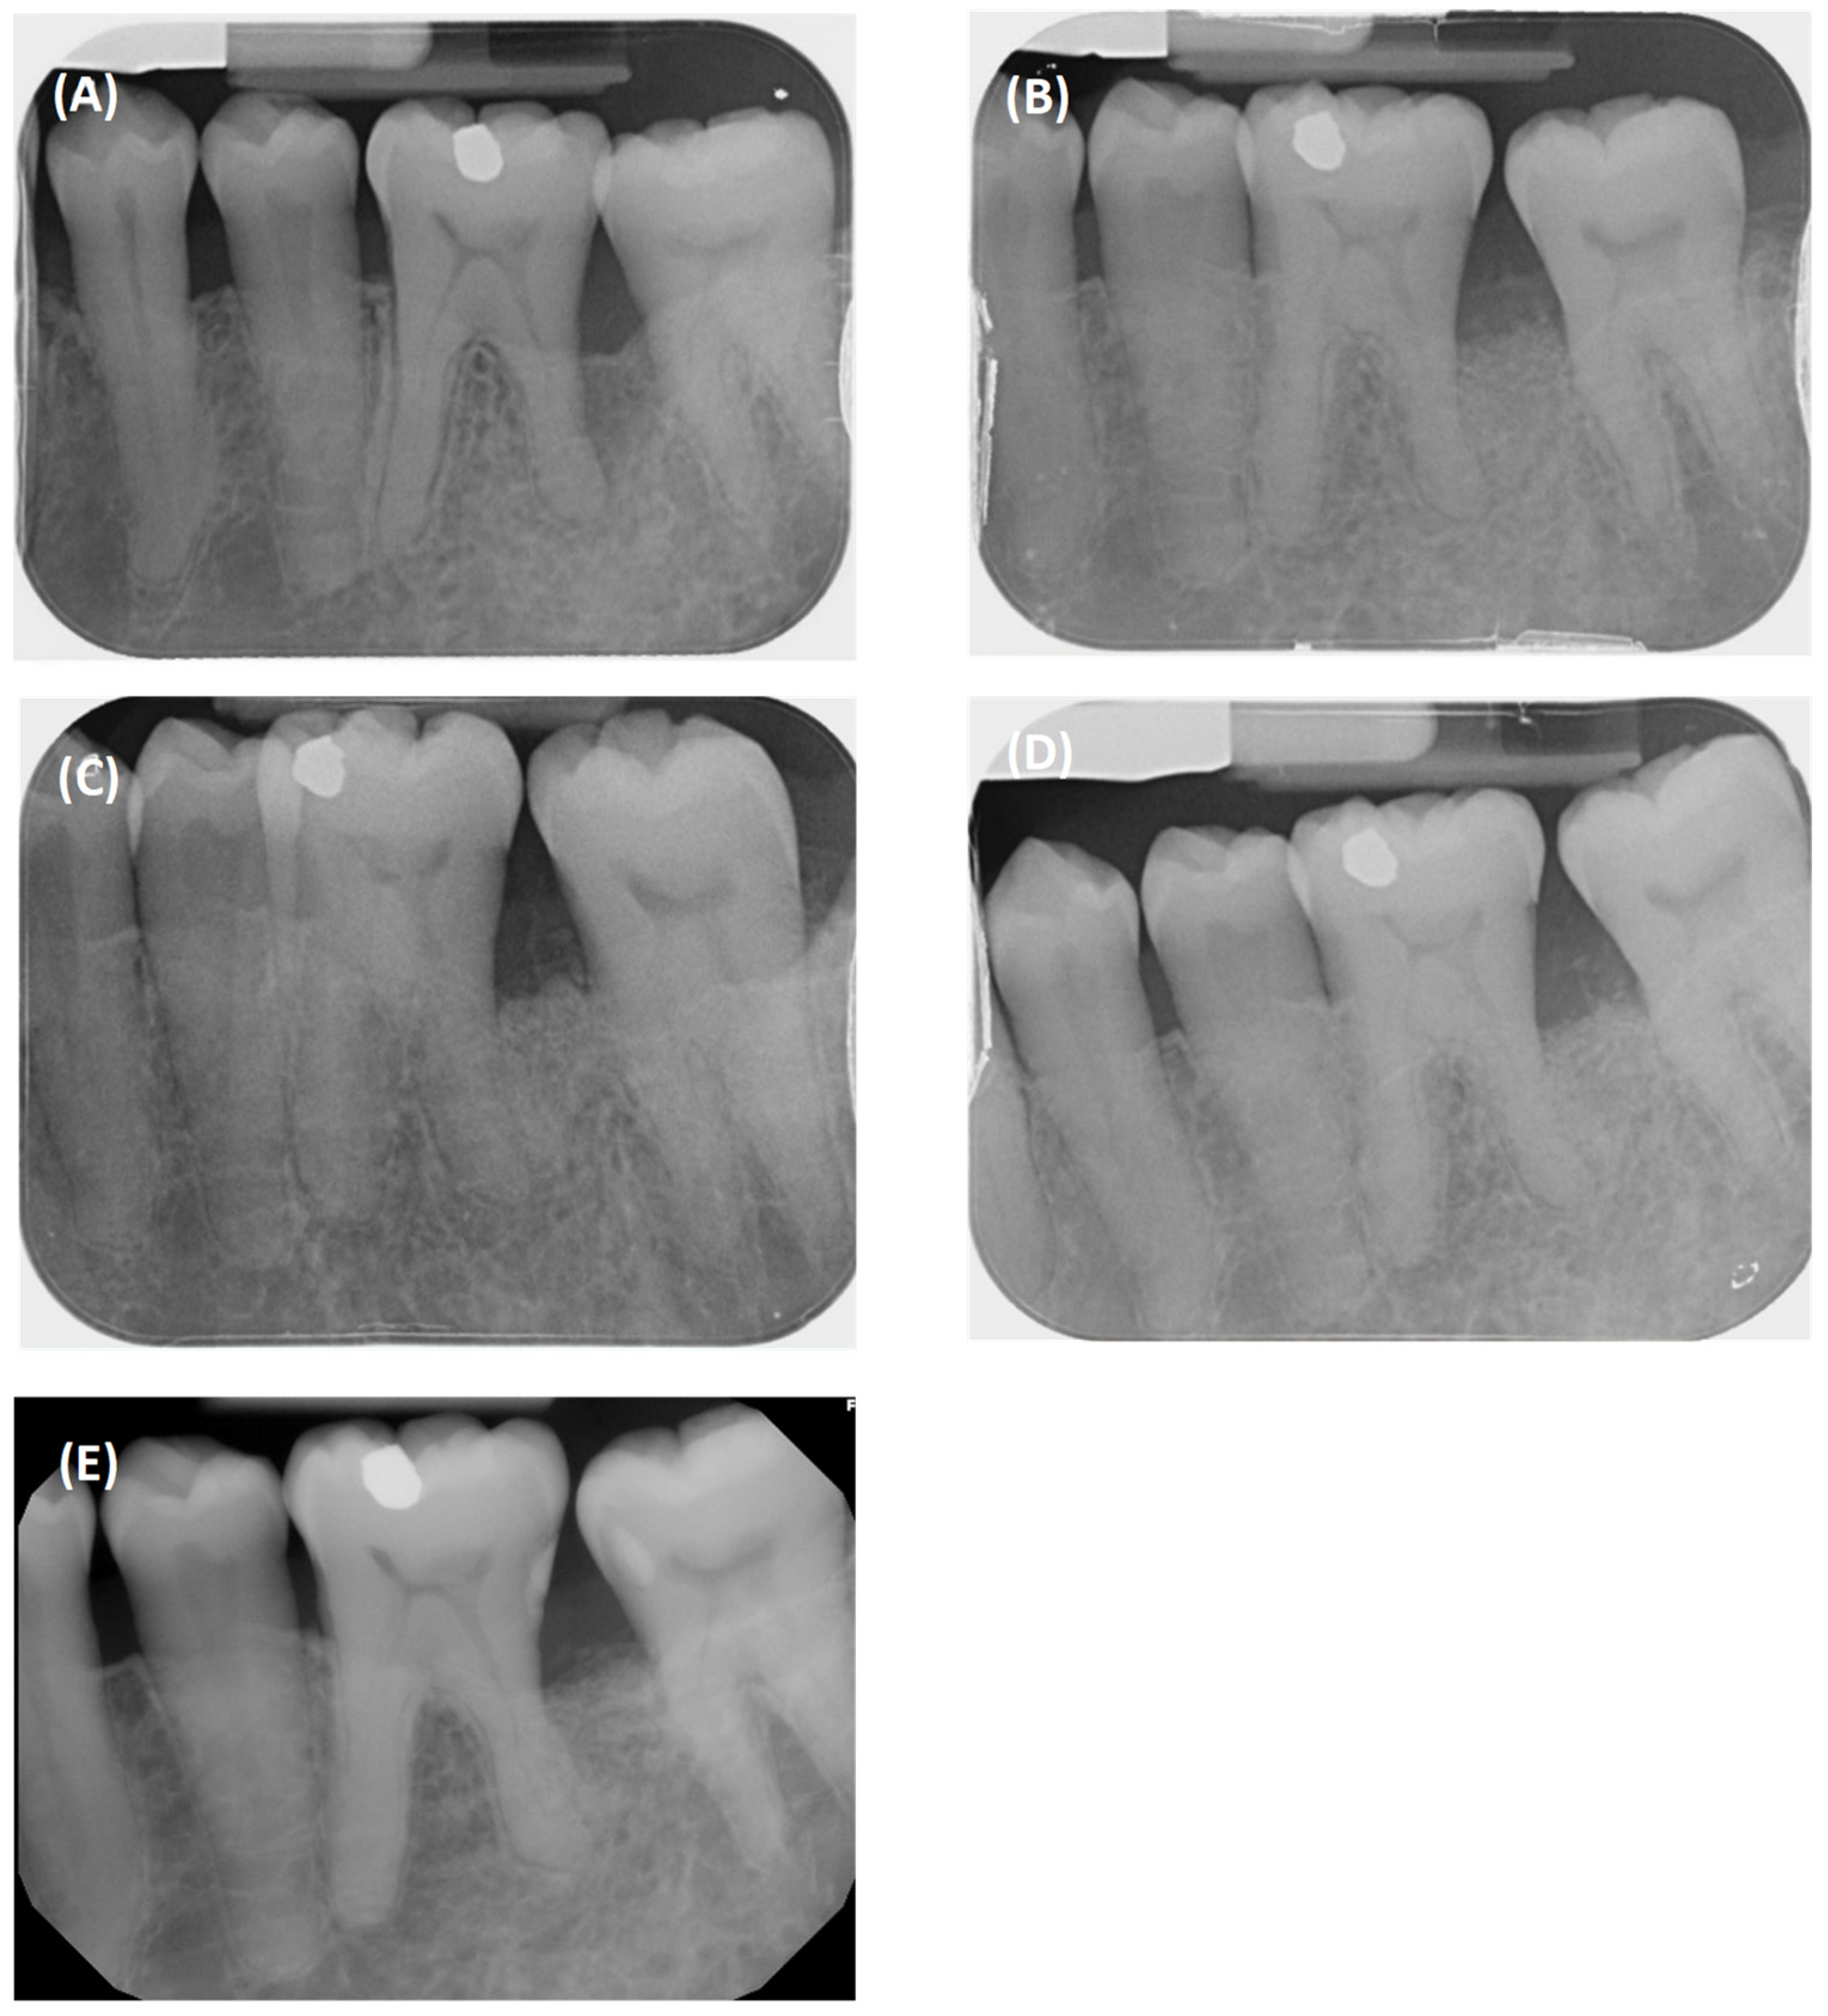

2.1. Case 1

2.2. Case 2

3. Results